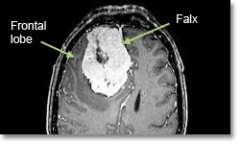

Meningioma Parafalcine

Location - Parafalcine (arising the meningeal layer between the hemispheres of the brain)

Common Symptoms

- Seizures, lower extremity weakness, headache, personality changes, dementia, increasing apathy, flattening of affect, unsteadiness, tremor.